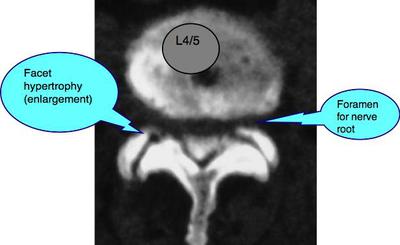

Obviously I can't examine you, but from both the initial injury and the fact that you get pain whilst arching your back points to a lumbar facet joint injury. This is normally bread and butter to a chiropractor, so the question is: why hasn't it responded to chiropractic help? I'm not sure. That short leg may be part of the problem.

You make no mention of leg pain which is a good sign, but I'm afraid it's coming if this isn't resolved. Those facet joints will become arthritic if the subluxation is not reduced, and then the proverbial stuff really hits the fan.